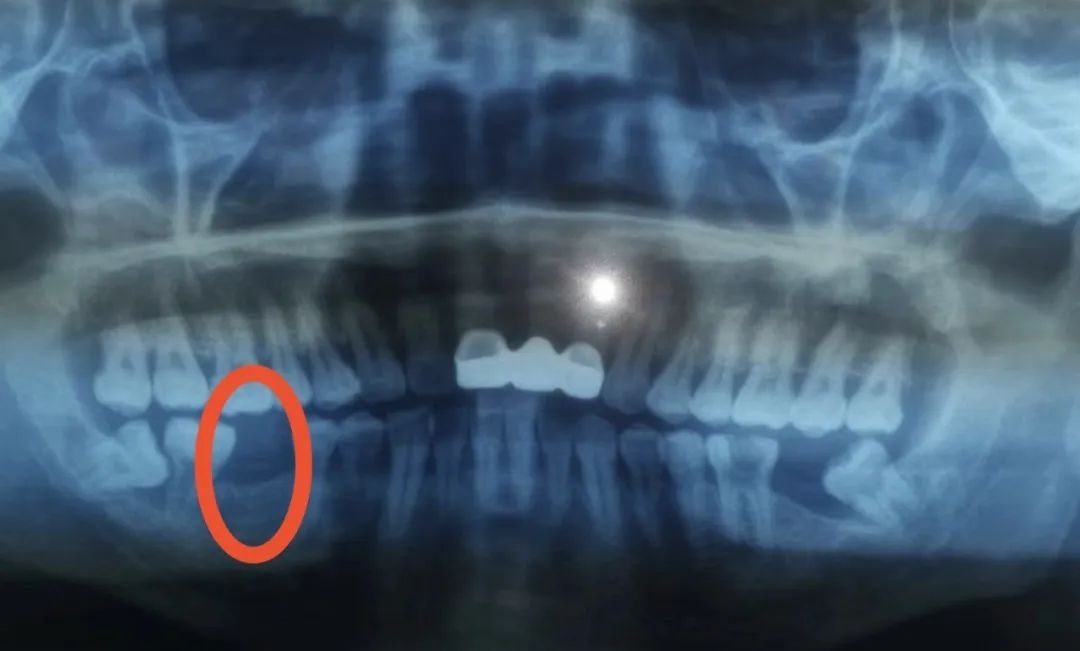

吴先生右下后牙缺失多年,给他造成了不小的烦恼,影响到了正常咀嚼功能。在九亭镇社区卫生服务中心口腔科就诊时了解到这里可以开展种植牙手术,经过仔细全面的口腔检查、检验等,医生认为吴先生符合种植牙条件,决定实施右下后牙区种植牙的修复方案。

本次手术由李国光副主任医师和方明医生共同完成,是该中心首例种植牙手术。手术历时约30分钟,术中微创操作,患者全程无痛,术后无不良反应,整个诊疗过程舒适、安全、精准。经术后检查种植体位置精确。

种植体位置精确